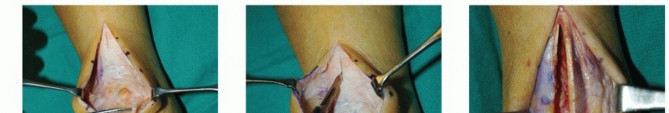

DEFINITION Tendinopathy of the Achilles tendon involves clinical conditions in and around the tendon arising …

DEFINITION Insertional and midsubstance Achilles tendinosis is a painful degenerative process that arises due…